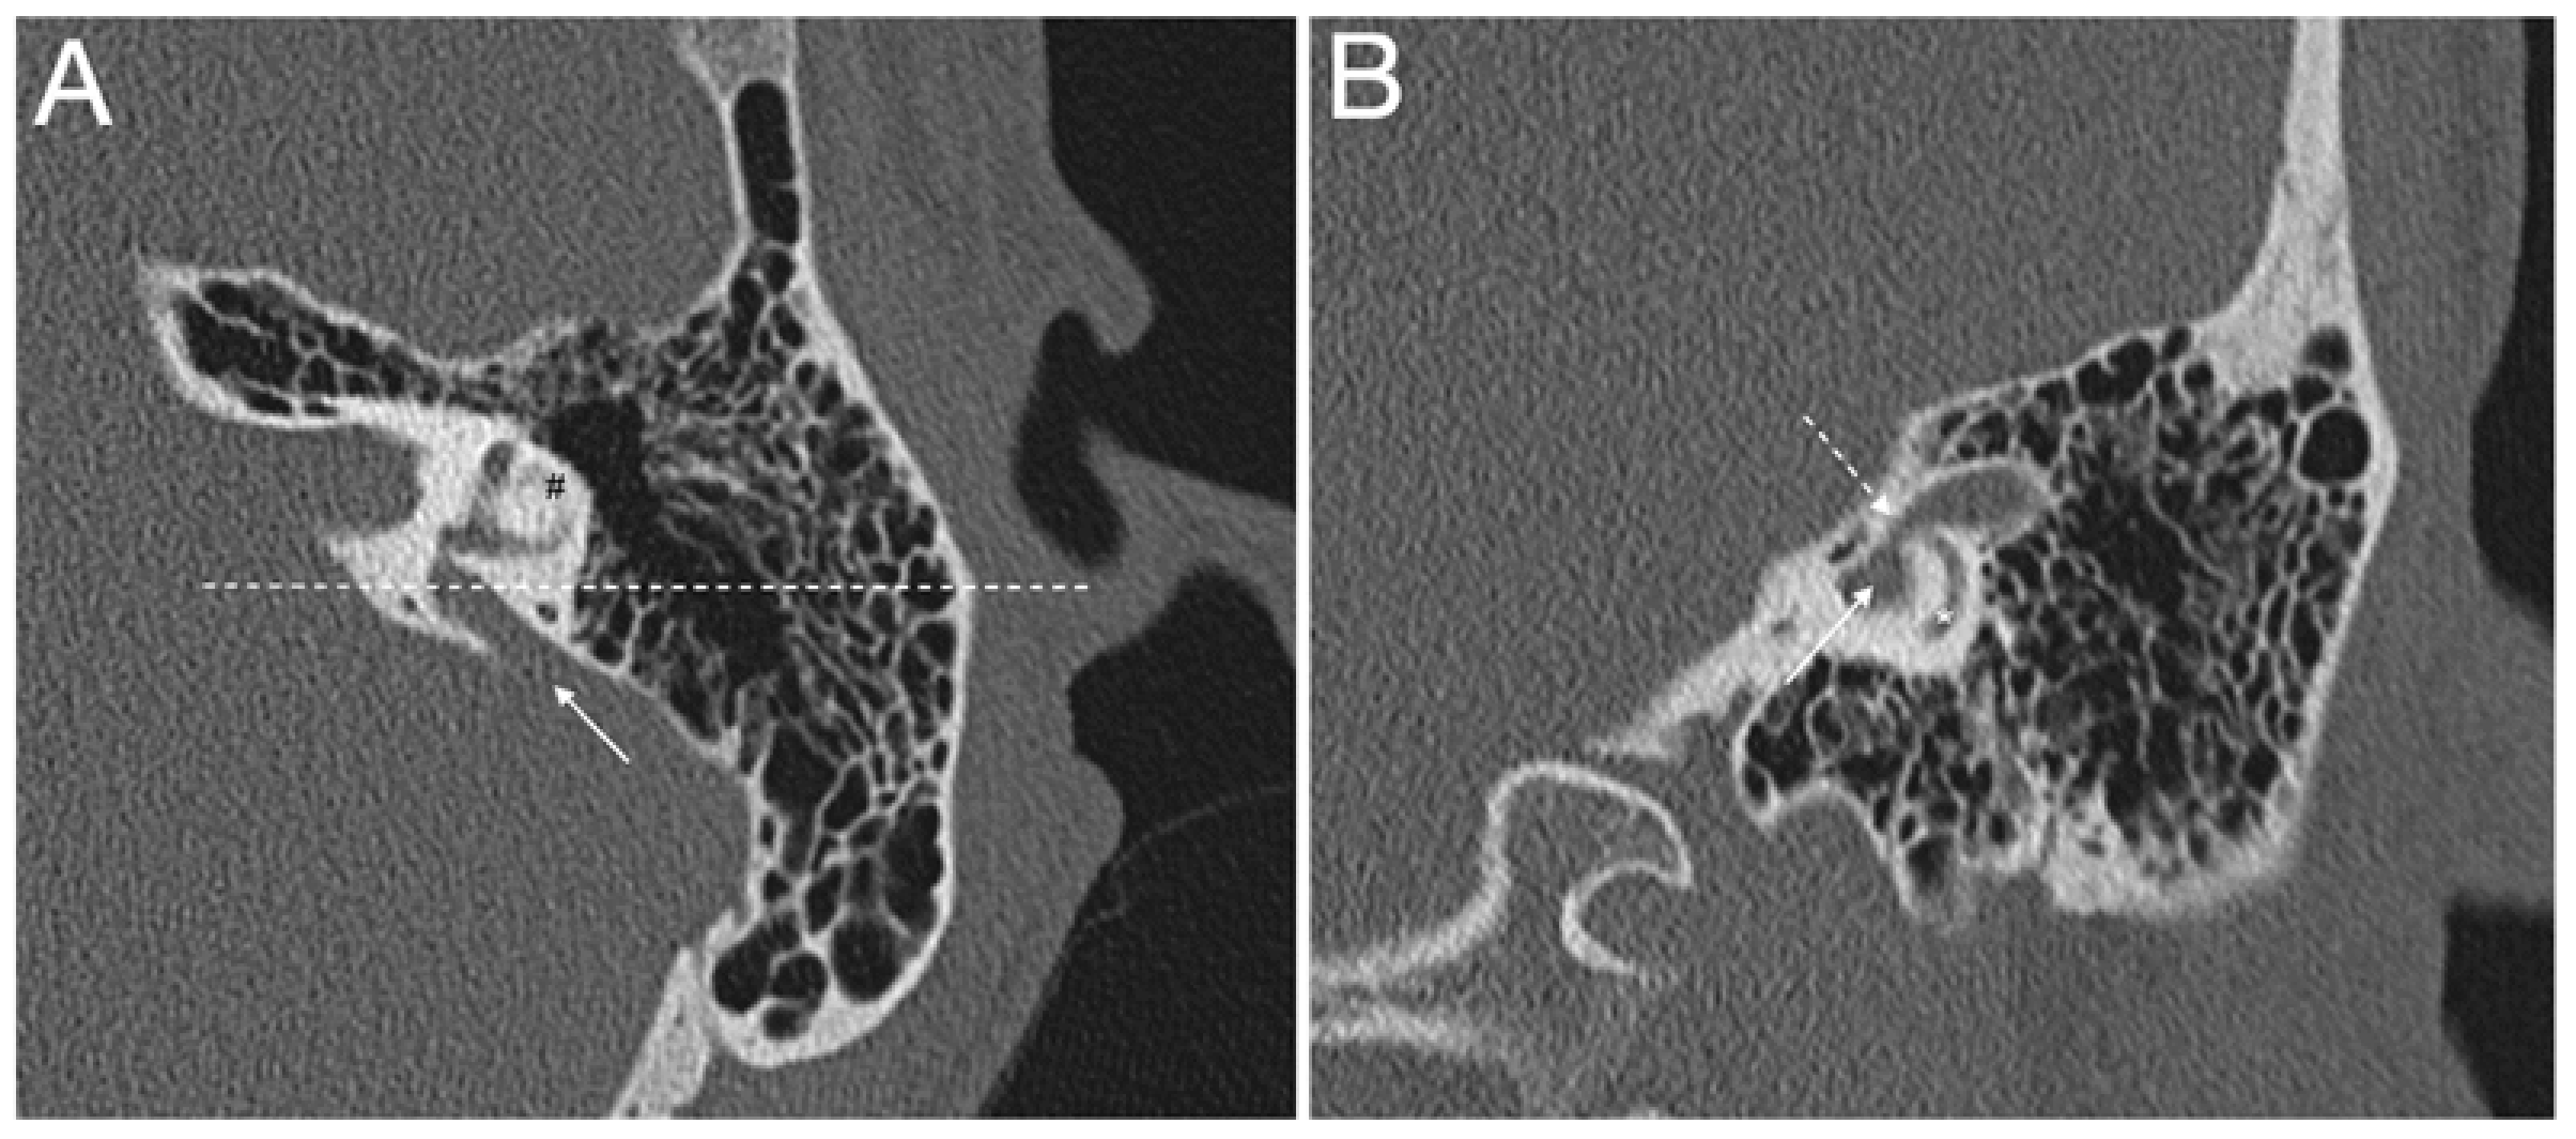

- Gong, W.X.; Gong, R.Z.; Zhao, B. HRCT and MRI findings in X-linked non-syndromic deafness patients with a POU3F4 mutation. Int. J. Pediatr. Otorhinolaryngol. 2014, 78, 1756–1762. [Google Scholar] [CrossRef] [PubMed]

- Choi, B.Y.; An, Y.H.; Park, J.H.; Jang, J.H.; Chung, H.C.; Kim, A.R.; Lee, J.H.; Kim, C.S.; Oh, S.H.; Chang, S.O. Audiological and surgical evidence for the presence of a third window effect for the conductive hearing loss in DFNX2 deafness irrespective of types of mutations. Eur. Arch. Otorhinolaryngol. 2013, 270, 3057–3062. [Google Scholar] [CrossRef]